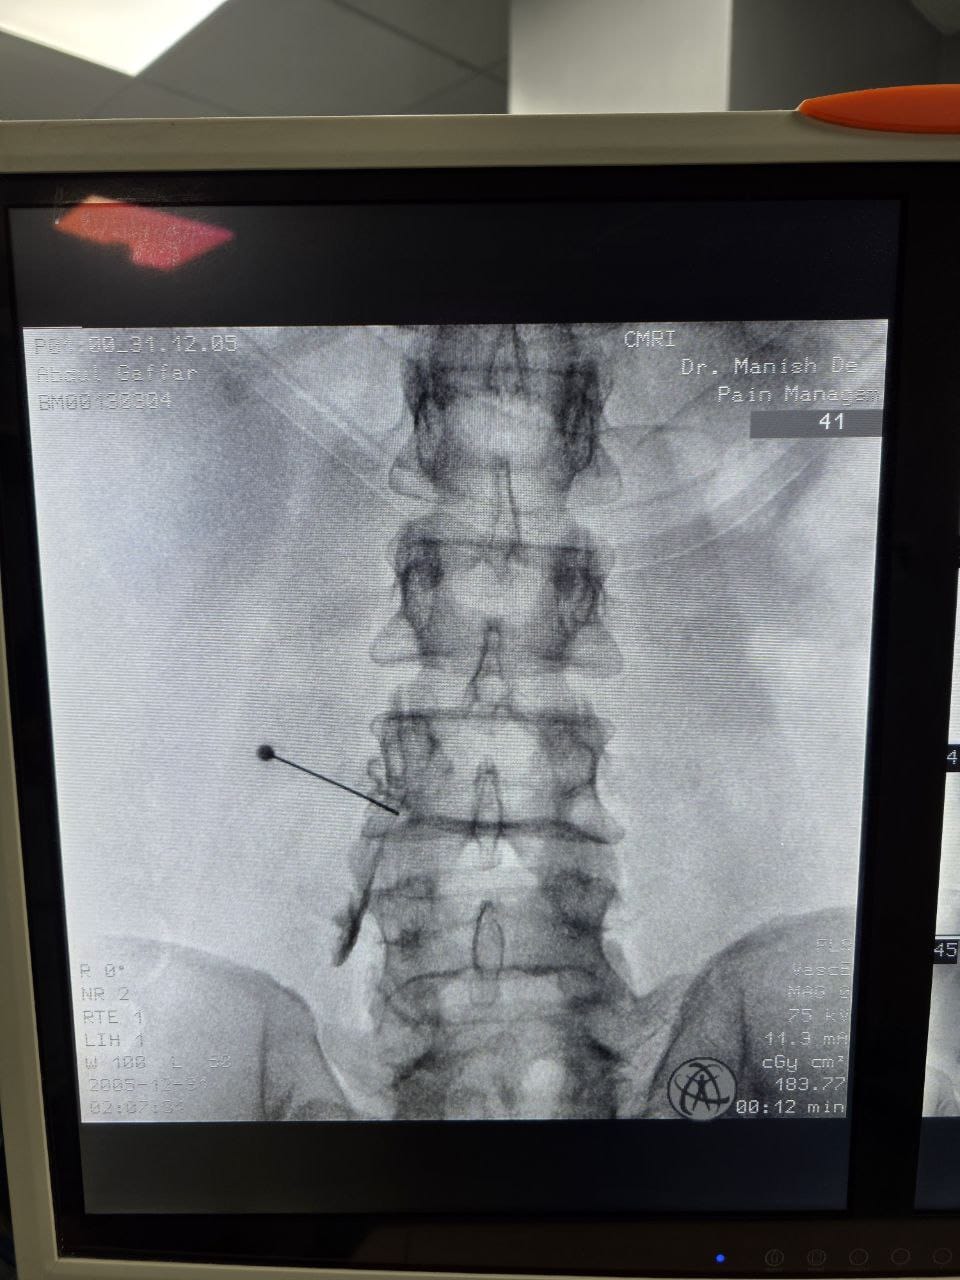

Procedures

Struggling with chronic pain? Get advanced, personalised pain management from Dr. Manish De, one of Kolkata’s leading pain specialists. From knee pain, heel pain, low back pain, frozen shoulder, migraines, cancer pain to post-TKR persistent pain—Dr. De offers safe, evidence-based treatments across multiple locations: